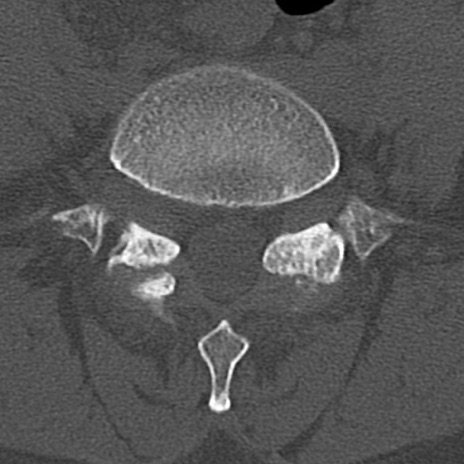

腰椎CT

横断像と矢状断像